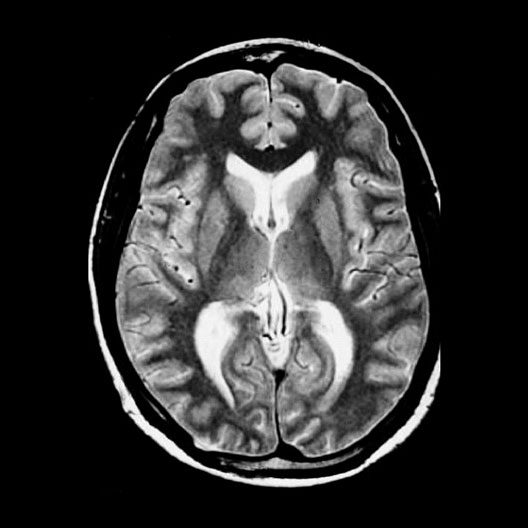

Head MRI Internal Capsules

Roll mouse over image to display labels.

1. Thalamus

2. White matter

3. Lateral Ventricles

4. Gray matter

5. Third Ventricle